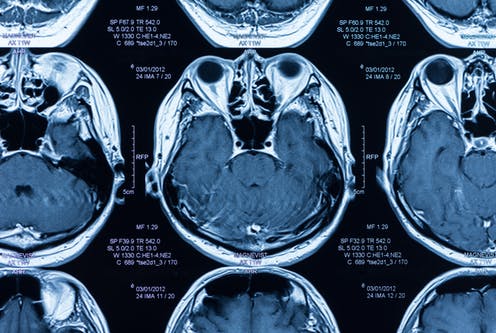

A tool that can help is an electroencephalogram, or EEG, which tests brain waves. Functional brain imaging, such as functional MRI, is another tool used to gain more insight into what is going on inside a brain by monitoring the change in activity of certain areas, especially, if no such “simple commands” can be executed.

In the recent study published in the New England Journal of Medicine, neurointensive care physicians – doctors who take care of patients with brain injury in intensive care – and researchers took brain wave analysis to the next level. They connected unresponsive patients with acute brain injury to continuous EEG, and asked them to perform simple commands while their brain waves were being recorded. The EEG data then were fed into a machine-learning algorithm derived from healthy volunteers, which compared the change in brain activity from the state while at rest to the activity recorded following the commands.